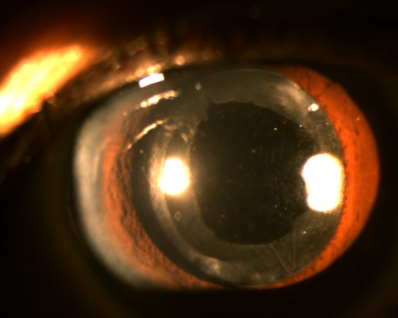

晶状体手术或晶状体外伤后,晶状体后面的囊壳发生混浊,即后发性白内障。窗帘虽然被拆了,但窗玻璃泛尘也是会影响光线的射入的,自然也会影响房间里的人看清窗外的风景。所以,后发性白内障又会让您看东西变得模糊了。

发生后发性白内障的时间不定,从白内障手术后3个月到4年不等。一般年龄越大,出现后发性白内障的可能性越小,儿童白内障术后,几乎百分之百的出现。想要泛尘的窗玻璃像原来一样透明,是不是要擦擦窗玻璃?现在的医学还做不到这样。那么,想要看见窗外的风景,只能把泛尘的窗玻璃取掉。治疗后发性白内障,就是把混浊的后囊膜切开一个直径约瞳孔直径大小的孔洞。

治疗影响视力的后发性白内障,首选激光后囊切开术治疗,如果因为壳太厚激光打不穿,也可以手术切开后囊膜。

Nd:YAG激光治疗后发性白内障,通过电离效应,在组织内形成等离子体,利用其爆破产生的冲击波使后囊膜破坏裂解,给后囊膜切开一个直径约2-4mm大小的小孔。就像隔山打牛,隔着一段距离,拳掌攻击,就能将牛击倒。Nd:YAG激光治疗后发性白内障,在门诊就可以做,不需要住院,做完就可以回家。点些眼药水就可以做,痛苦小,操作简单,最快1-2分钟就可以做完,眼球表面没有切口,成功率高,视力恢复快,疗效确切,并发症小,是目前治疗后发性白内障的首选方法。